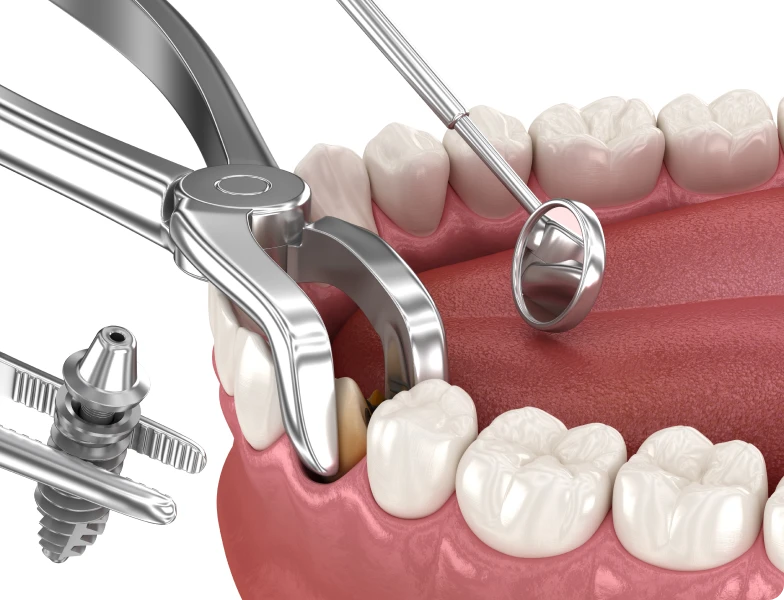

L’extraction implantation immédiate est une approche qui consiste à poser un implant dentaire le jour même de l’extraction d’une dent. Autrement dit, l’implant est inséré dans l’alvéole (logement osseux de la dent) immédiatement après le retrait de la dent naturelle.

Étape 1 : extraction atraumatique

La dent à retirer est extraite avec une technique douce, sans altérer les parois osseuses qui l’entourent. Cette extraction atraumatique est essentielle pour préserver le site d’implantation. Elle limite le risque de résorption osseuse et favorise l’intégration future de l’implant.

Étape 2 : mise en place de l’implant

Immédiatement après l’extraction, l’implant est inséré dans l’alvéole. Selon les cas, un matériau de comblement peut être ajouté autour de l’implant pour stabiliser le site. La stabilité primaire (c’est-à-dire la fixation mécanique immédiate) doit être suffisante pour assurer une bonne ostéointégration.